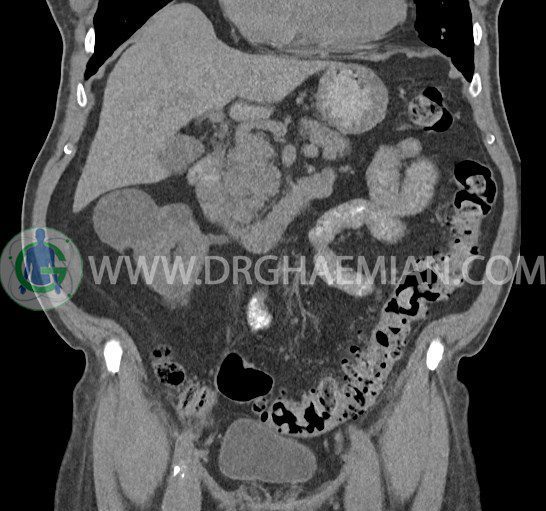

سی تی اسکن لگن یکی از روش های تصویربرداری با سی تی اسکن است. این روش با استفاده از تشعشعات تصاویر عرضی از ناحیه شکمی ایجاد میکند. در این کیس ديورتيكولوزيس، کیست های کورتیکال در هر دو کلیه، لنفادنوپاتی، کلسیفیکاسیون دیواره آئورت و شریان ایلیاک، تغییرات DJD ناحیه توراکولومبار و پروستات بزرگتر از عادی دیده می شود.

در سي تي اسکن اسپيرال شکم و لگن با و بدون کنتراست خوراکی و وريدی (مولتي ديدکتور 16 با مقاطع ظريف و بازسازي هاي ساژيتال و کرونال):

– کيست هاي کورتيکال ساده به قطر 5 mm تا 50 mm در کليه راست و به قطر 5mm تا 55 mm در کليه چپ

– توده ايزودنس به ابعاد mm 17 x 28 در پره ائورت مجاور قسمت تحتاني D3 دئودنوم مطرح کننده لنفادنوپاتي و با احتمال کمتر آنوريسم ترومبوزه (نيازمند مطابقت سونولوژيک)

– کلسيفيکاسيون ديواره آئورت و شريان ها ايلياک همراه با نشانه هاي ترومبوز مورال در بيفورکاسيون ائورت با امتداد به پروگزيمال هاي شريان هاي ايلياک

– ديورتيكولوزيس در کولون نزولي وسيگموئيد

لنفادنوپاتي به ابعاد mm 22 x 25 مجاور شريان ايلياک خارجي چپ و به ابعاد mm 17 x 28 مجاور شريان ايلياک خارجي راست

– تغييرات DJD در ناحيه توراکولومبار و

– پروستات به ابعاد mm 45 x 54، بزرگ تر از نرمال

مشهود است.